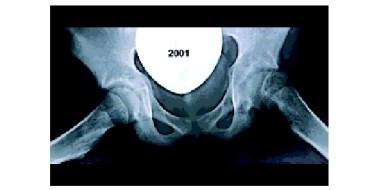

• Epifysiolyse van het caput femoris

Zelfs na röntgenonderzoek wordt de diagnose epifysiolyse van het caput femoris (het afglijden van de femurkop) nogal eens gemist; de eerste twee casus zijn hier voorbeelden van. In het derde geval werd de diagnose wel gesteld, maar werd de patiënt niet met spoed doorverwezen. Bij alledrie de…